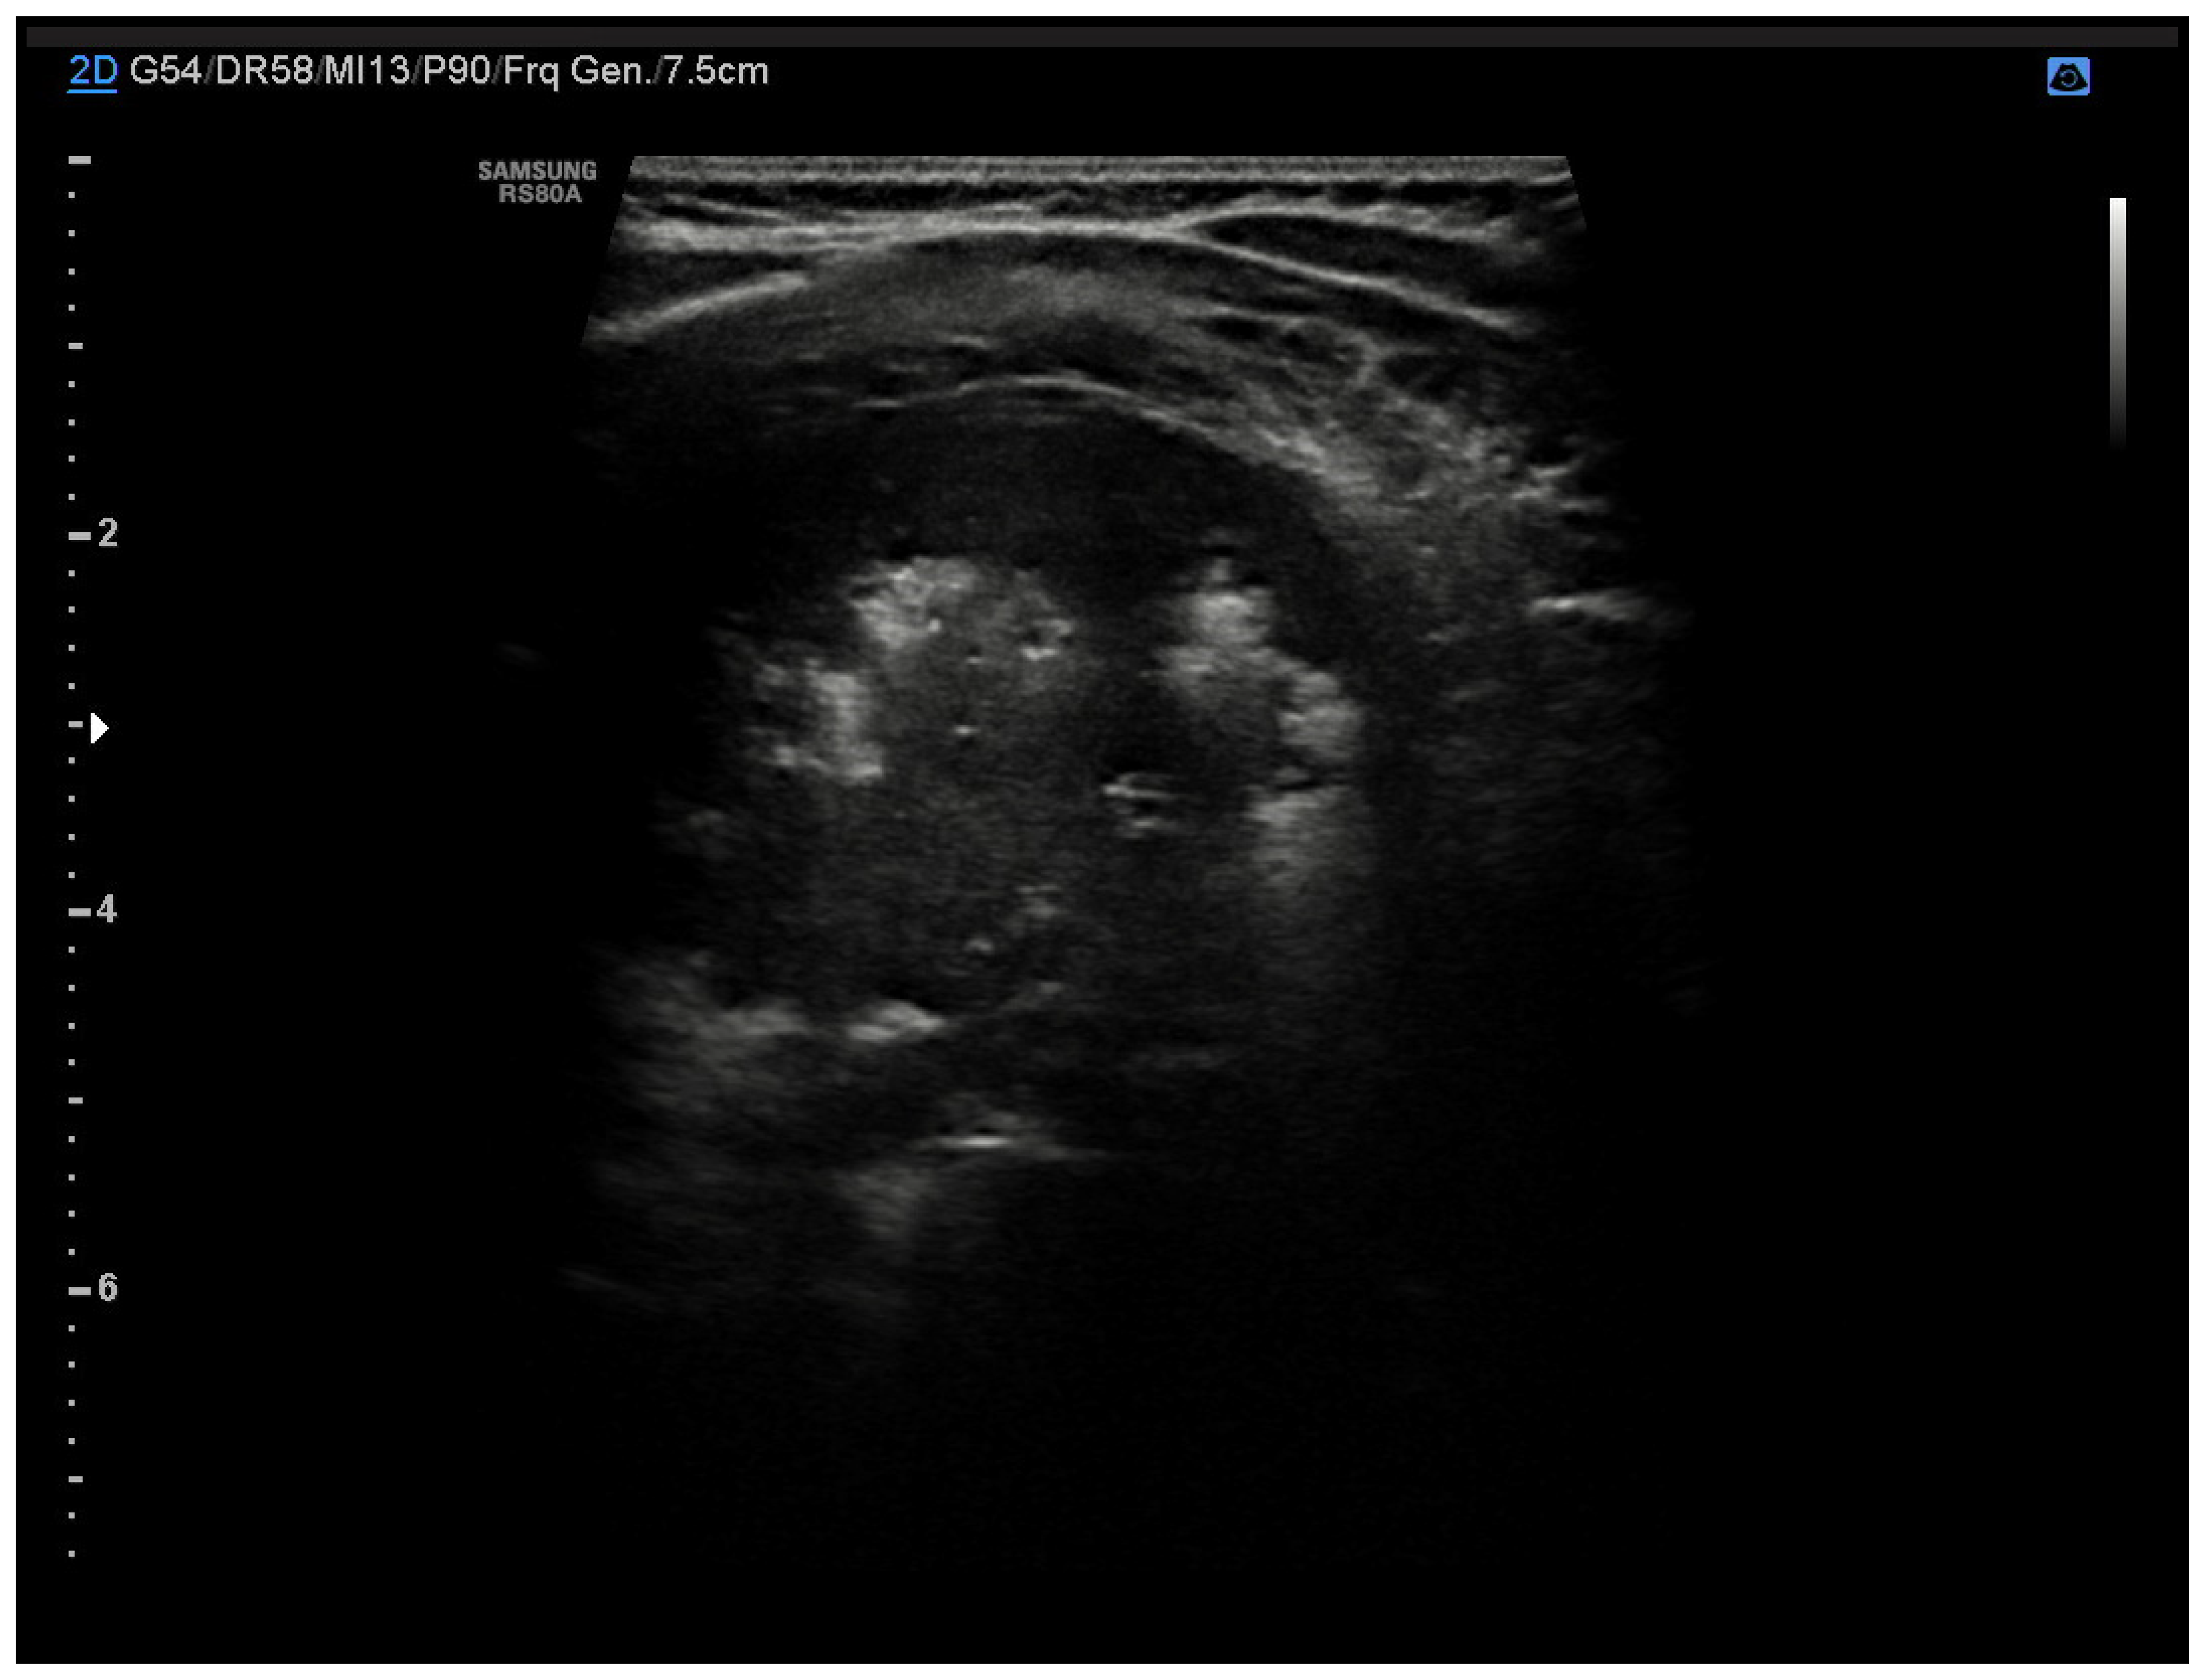

4.2. Pneumonia

4.6. Pleural Pathologies and Complications of Pneumonia

- Jaworska, J.; Komorowska-Piotrowska, A.; Pomiećko, A.; Wiśniewski, J.; Woźniak, M.; Littwin, B.; Kryger, M.; Kwaśniewicz, P.; Szczyrski, J.; Kulińska-Szukalska, K.; et al. Consensus on the Application of Lung Ultrasound in Pneumonia and Bronchiolitis in Children. Diagnostics 2020, 10, 935. [Google Scholar] [CrossRef] [PubMed]